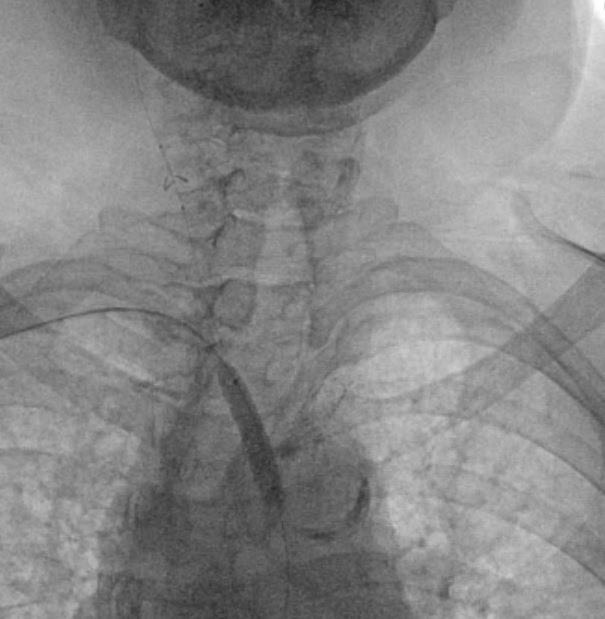

At this moment we elected to proceed with endovascular intervention through the radial access. Via right radial access, a long Runthrough wire (Terumo Interventional Systems) crossed the stenosis into the distal aorta, and we upgraded the sheath to 7F over both wires (BareWire and long Runthrough). We exchanged the long Runthrough wire with a Glidewire Advantage (Terumo Interventional Systems) via a TrailBlazer support catheter (Medtronic). We predilated with an 8-mm balloon and then an 8-mm x 29-mm Omnilink ballon-expandable stent (Abbott Cardiovascular) was successfully placed in the right innominate artery and deployed (Figure 3). Next, a pigtail catheter was advanced through the groin and angiography was performed, showing an under-expanded and malapposed mid to distal area of the stent (Figure 4), which was post-dilated with a 14-mm x 10-mm Armada balloon (Abbott Cardiovascular) (Figure 5), after which the filter was removed and a final aortogram showed good results with better apposition without complications (Figure 6).